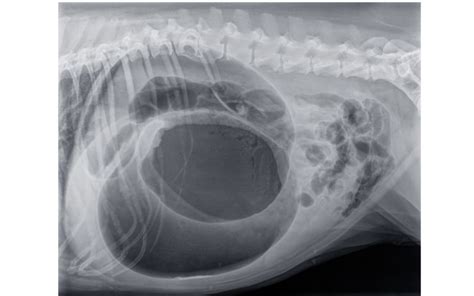

Môže sa stať aj to, že zožratý predmet sa do čriev ani neposunie a zostane v žalúdku, kde môže vyvolávať problémy. Preto sa odporúča návšteva veterinára a skonzultovanie, prípadne žiadanie sono či RTG vyšetrenia žalúdka a čriev.

Je otazné, či pes predmety rozhryzol, potrhal a zjedol. V takom prípade máte šancu, že to aj nejakým spôsobom z neho vyjde. Ak to zhltol vcelku, je vysoká šanca, že budú problémy. U psa veľkosti jazvečíka to cez črevo prebehne vcelku len so zázrakom.

Je lepšie ísť na veterinu hneď, keď sa také niečo stane. Kým je to v žalúdku, dajú injekciu na zvracanie, pes to vyzvracia a nejde to ďalej. Akonáhle to prejde do čreva, ale zároveň črevo nebude schopné to celé posunúť až von, nastane nepriechodnosť čriev. Nepôjde to ani dopredu, ani dozadu, a psa bude treba operovať.